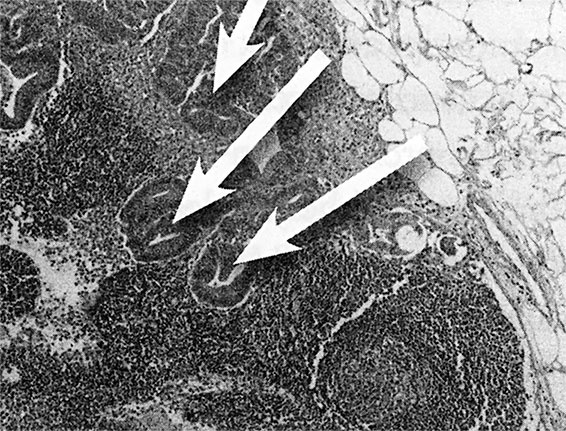

Пролистнем следующие несколько тысячелетий, в течение которых рак продолжал поражать тела молодых и стариков. Одним из проницательных и наблюдательных врачей во времена Античности был римский физиолог, хирург и писатель Гален. Он предложил теорию заболеваний в то время, когда такие дисциплины, как анатомия, патофизиология и фармакология, находились в зачаточном состоянии. Медик II века н. э. Гален внес серьезный вклад в понимание патологии по Гиппократу. Гиппократ, как вы помните из школьного курса биологии, считается отцом медицины и разработчиком многих теорий в области здоровья (Афины, примерно 400 г. до н. э.). Физиологические и философские наблюдения Гиппократа легли в основу современной медицины. Современные медики считают его первым человеком, который поверил в то, что заболевания вызываются естественными причинами, а не воздействием колдовства или высших сил. Более того, он впервые зафиксировал различия между доброкачественными и злокачественными опухолями. Для описания опухолей разных частей тела, перерастающих в язвы, Гиппократ ввел понятие karkinos (греч. «краб»). Не очень понятно, почему раковая опухоль похожа на краба, но образ подошел. Гиппократ видел и описывал опухоли, вокруг которых были пучки воспаленных кровеносных сосудов, что и навело на мысль о крабе, закопавшемся в песок и выставившем конечности наружу. То, что Гиппократ описывал раковую опухоль как «похожую на краба», явно свидетельствует о том, что он не знал о видах рака, которые нельзя увидеть невооруженным взглядом. Чаще всего он видел большие опухоли на поверхности тела или близко к поверхности, такие как опухоли молочных желез, кожи, шеи и языка. Идеи Гиппократа в области здоровья и болезней позволили его последователям, таким как Гален, развивать их и ставить эксперименты. Некоторые эти эксперименты помогли дать точное определение рака. Гален описал его как неуправляемую и безжалостную часть тела. По его мнению, к раку приводил излишек обычной «черной желчи», которую невозможно убрать. Черная желчь поражала все тело, а опухоли отражали силу и упорство этого распространяющегося злокачественного состояния. Попытки вырезать такие опухоли не приведут к успеху, считал античный врач, так как черная желчь не только заполнит рану, но и приведет к развитию еще одной опухоли. У Галена не было изощренных терминов и инструментов вроде современных микроскопов и установок секвенирования генома, но он точно описал системную природу рака и его способности расти, давать метастазы и восстанавливаться. Многие идеи Галена сохранили свою актуальность до Возрождения, а студенты-медики продолжали изучать его труды до XIX века. Потом, когда патофизиологи XIX века направили микроскопы на внедрившиеся клеточные массы, они поняли жестокую шутку, которая и определяет природу рака: это избыток собственных клеток, а не черной желчи. Но эти клетки похожи на черную желчь, так как ведут себя как мятежники, которые рушат границы и грабят остальные клетки. Раковые клетки похожи не только аномальной формой, но и безудержной пролиферацией – бесконтрольным клеточным ростом. Сидхарта Мукерджи красиво описал этот процесс в книге «Король всех недугов», которая описывает место рака в истории человечества. На молекулярном уровне рак появляется после мутации генов конкретной клетки. Мощные генетические сигналы нормальных клеток указывают, когда и как клетке делиться. Некоторые гены активизируют размножение клеток, работая как педаль газа. Другие работают как молекулярные тормоза, останавливая рост. Это объясняет, в частности, почему, например, когда заживает царапина на коже, клетки, задействованные в заживлении, «знают», когда нужно останавливать развитие новых клеток, так чтобы не оставить вас с опухолью из новой кожи. Но в раковой клетке нет этого отточенного баланса между активным ростом и неактивностью. Светофор, который управляет ростом клеток, не работает или слишком часто дает зеленый свет. Клетки, соответственно, остаются без регулирования и не знают, когда прекращать рост. Но такой взгляд на рак на молекулярном уровне не является единственным полезным инструментом в подборе лечения. Для меня рак (рис. 4) выглядит примерно так: ![]() А. Печень человека с метастазами рака толстой кишки ![]() Б. Аксиальная компьютерная томография, показывающая наличие метастазов рака в печени ![]() В. Рак в лимфоузле под микроскопом Вот мы видим А – печень с раком толстой кишки, что правильнее назвать «метастазы рака толстой кишки в печень». Рак переместился, метастазировал, из толстой кишки в печень, что подтверждается белыми образованиями на снимке. Б – томограмма другой печени, пораженной раком толстой кишки («метастазы рака толстой кишки в печень»). Обратите внимание на пять круглых темных образований в левой части изображения. И В – изображение рака толстой кишки в лимфоузле под микроскопом («метастазы рака толстой кишки в лимфоузел»). Пояснение: «рак толстой кишки», который метастазировал в легкие, не будет называться «рак легких». Это все еще рак толстой кишки и выглядит он как рак толстой кишки. Рак – это взаимодействие клетки, лишенной контроля роста, с окружающей средой. Для понимания рака важнее обратить внимание на то, что это не только неконтролируемое деление клеток и их распространение. Важнее другая характеристика – способность изменяться со временем. Хотя люди часто представляют себе рак как сошедшую с ума машину для копирования клеток, не вносящую изменений, в действительности он гибче и динамичнее. Каждый раз, когда появляется новое поколение злокачественных клеток, в них появляются новые мутации – которые еще сильнее меняют гены, отвечающие за рост клетки. Хуже того: в опухоли после химиотерапии могут остаться клетки, резистентные к лекарственным средствам. Другими словами, так же, как после применения антибиотиков появляются резистентные бактерии, противораковые средства могут стимулировать появление резистентных раковых клеток. Но вновь отстранимся от молекулярной точки зрения на рак. Как видно, эволюция влияет на проявления рака, но не на генетику. Да, за злокачественные опухоли отвечают разные гены, но внешний вид получается одинаковым. Да, могут существовать 50 различных молекулярных путей развития того или иного новообразования, например, рака молочной железы, толстой кишки, легких, мозга или простаты, но в итоге результат и способ действия оказываются одинаковыми. Если показать гистологу десять образцов рака молочной железы от разных пациентов, то молекулярная основа во всех случаях будет разной, но под микроскопом все будет выглядеть как рак молочной железы. Аналогично наблюдается удивительное сходство между видом клеток рака молочной железы и клеток рака любого другого органа, потому что у злокачественных клеток много общего во внешнем виде и поведении. Это – важнейший момент в понимании рака. Ученые долго изучали молекулярные дефекты, ведущие к раку, но не сам его вид. Описание от Национального института рака (стр. 49) составляет только часть общей картины. Рак – это не генетическое заболевание. Скорее это болезнь, при которой клетки начинают выглядеть и вести себя определенным способом, используя для этого генные мутации. И если при разработке новых методов лечения будет найден способ блокирования одного молекулярного пути, то это не означает, что рак не найдет другого (что, к сожалению, он обычно успешно проделывает). |